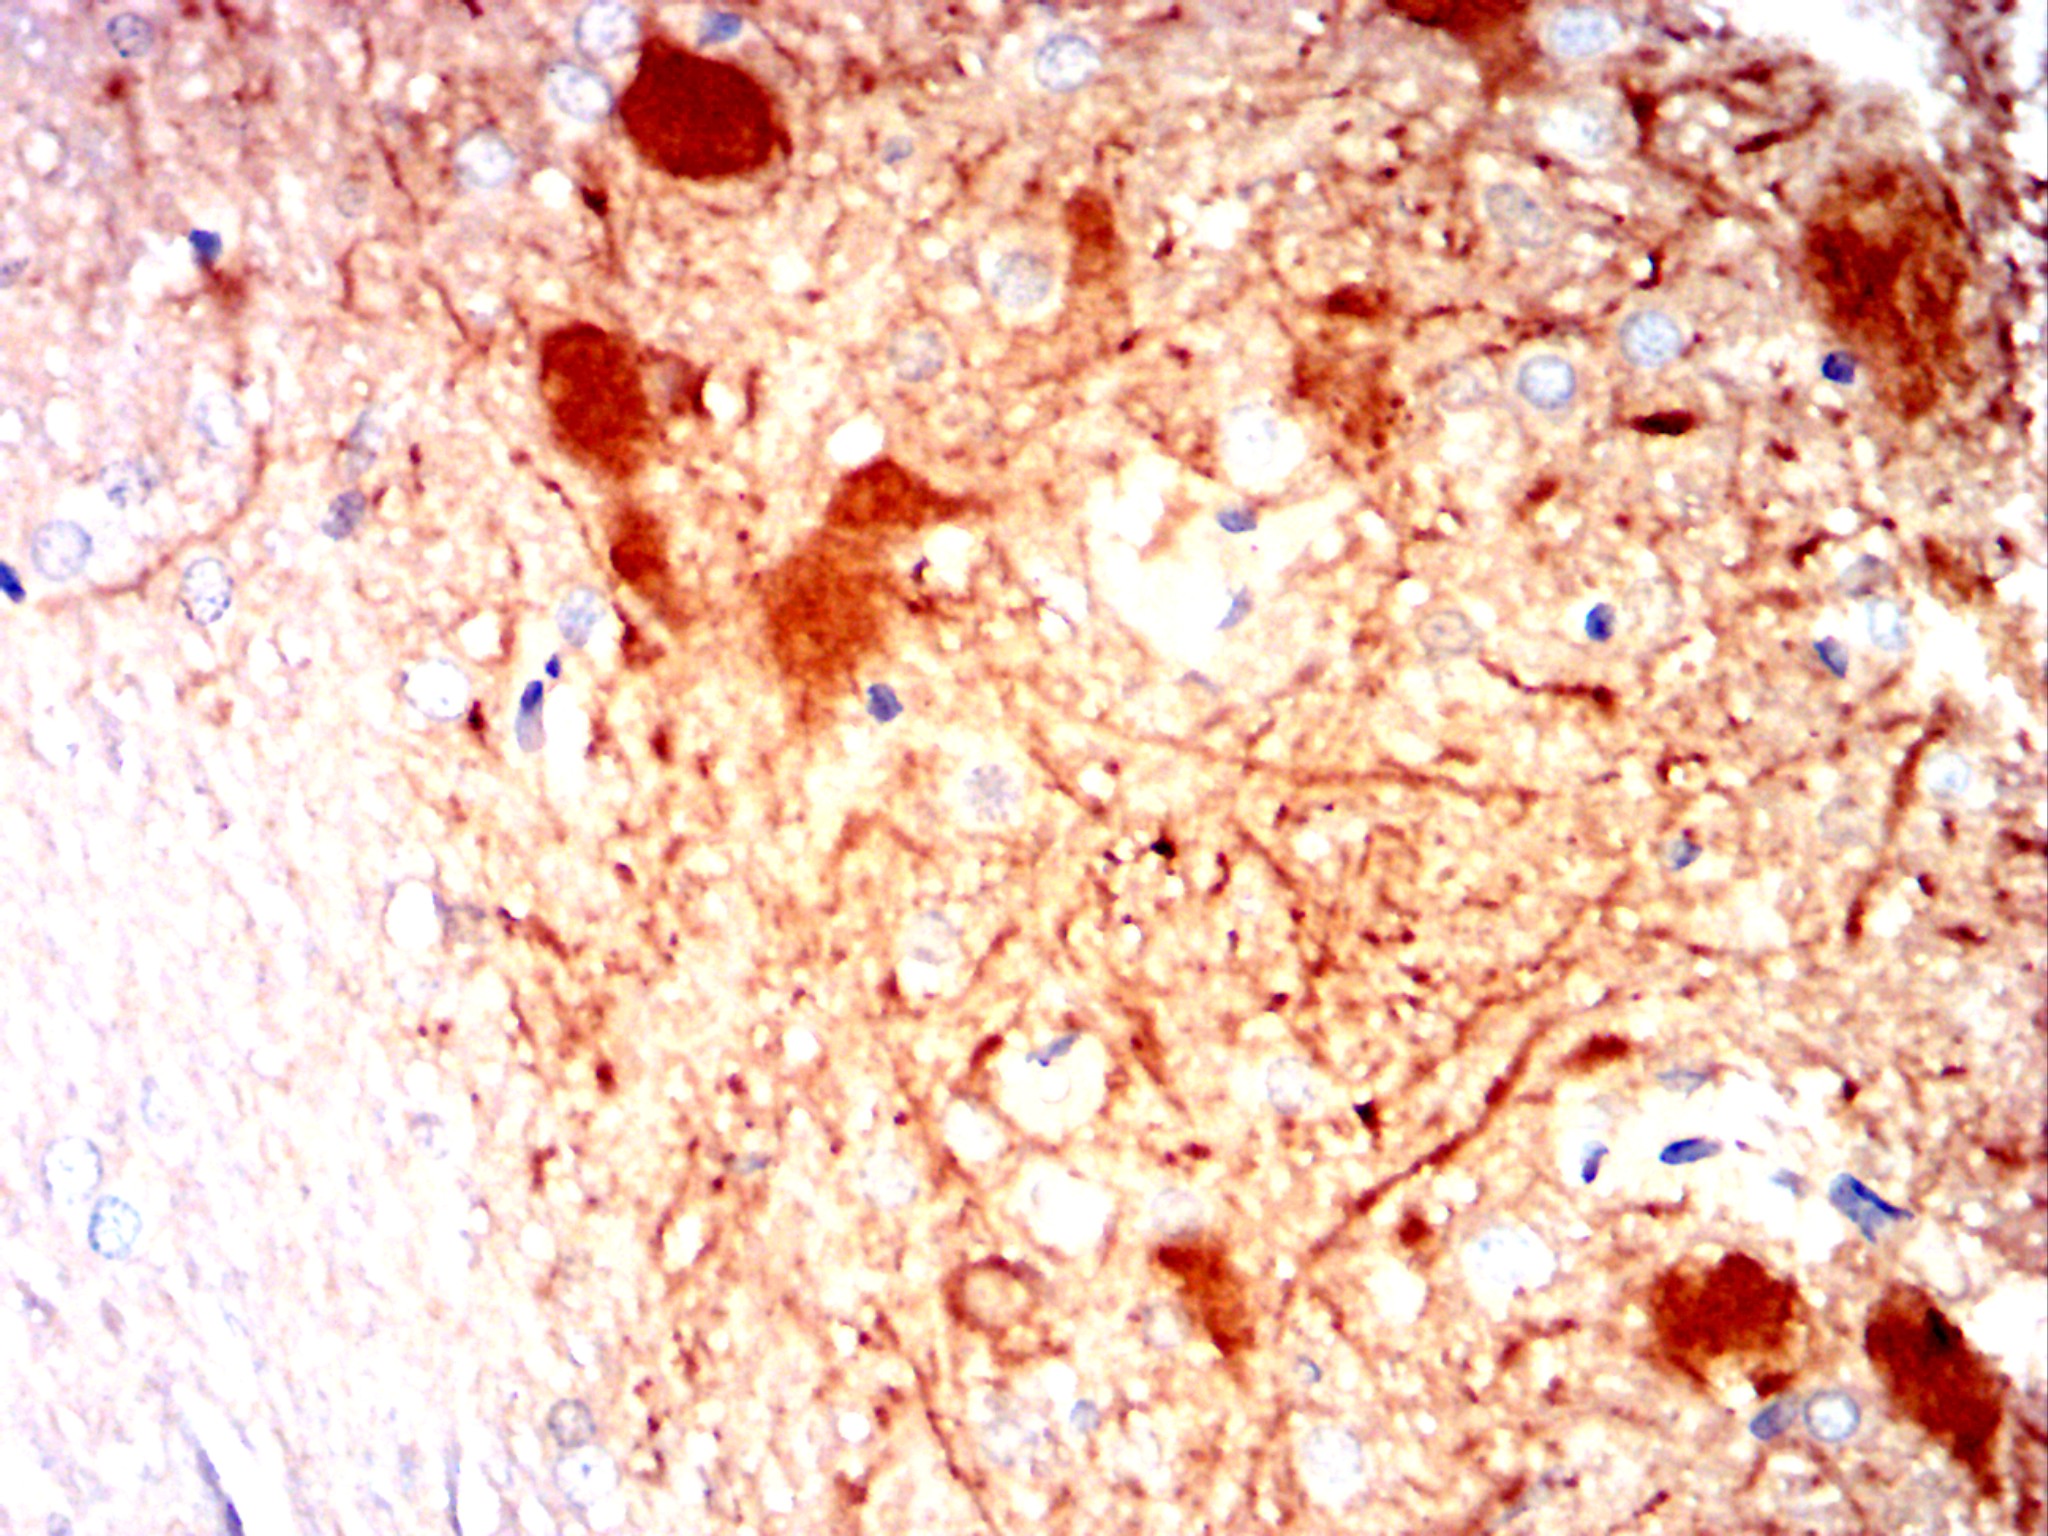

![CAMK2G Mouse mAb[63190]](https://img1.dxycdn.com/p/s14/2025/0922/244/8482471802292699691.jpg)